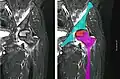

Nuclear magnetic resonance of avascular necrosis of left femoral head. Man of 45 years with AIDS.